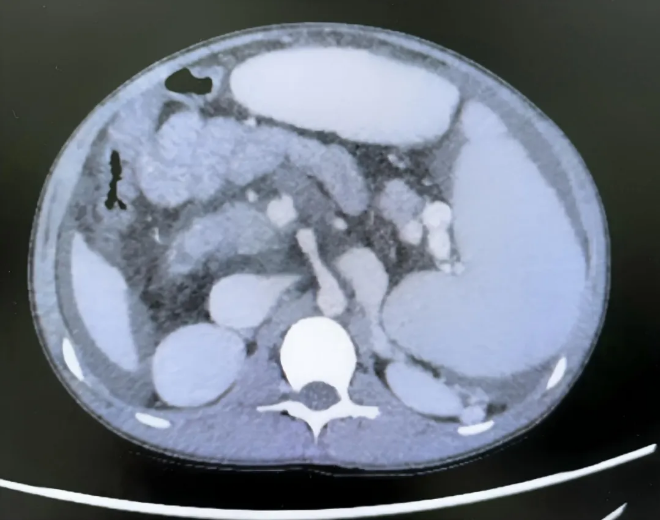

入院后血液检查结果显示,小李患有极重度贫血,血红蛋白仅25g/L(正常参考值120g/L以上),已处于休克边缘;血小板计数极度低下,仅16×10⁹/L(正常参考值100-300×10⁹/L)。影像学检查提示,其脾脏异常巨大,边缘已从腹腔左侧延伸至右侧,占据腹腔大部分空间。

住院期间,小李完善了超声及增强CT检查,明确诊断为门静脉海绵样变,其脾脏肿大程度在门脉高压患儿中极为罕见,此类巨大脾脏通常多见于血液系统疾病患儿。为排除血液系统疾病,团队联系血液科会诊,结合骨髓穿刺结果及血液病相关血液筛查报告,最终排除血液系统疾病可能,确认脾大、脾亢症状仍由门静脉海绵样变所致门脉高压引起。

图1 CT显示脾脏显著增大